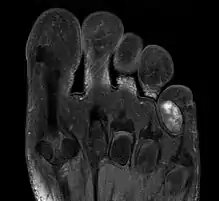

| Chondroma of the soft parts located in the little toe. | |